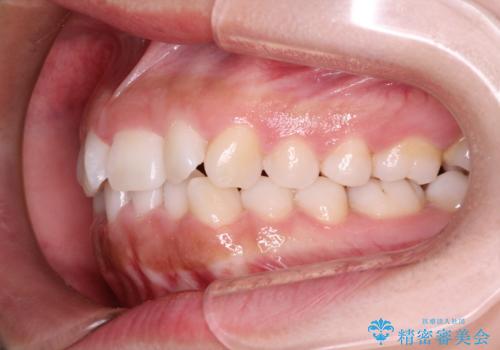

- 初診時には前歯部に捻転や叢生、臼歯部にも一部叢生が見られる状態でした。

インビザラインでの治療を計画し、行っていきました。

インビザライン治療により、捻転を含む歯列もしっかりと改善しています。